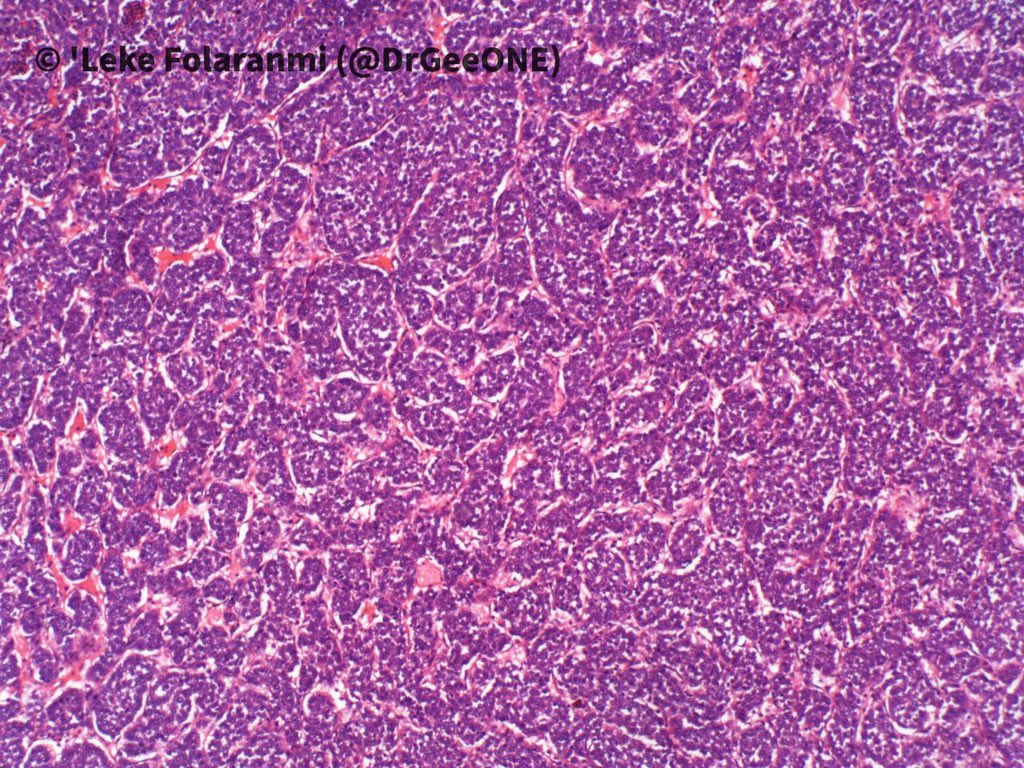

A male in his 20s with huge intrathoracic mass.

Duration: 2 years

❗️No IHC done

Our list of differentials:

-Ewing Sarcoma

-DSRCT

-Synovial Sarcoma

-Mesenchymal chondrosarcoma